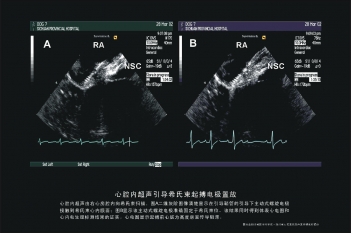

希氏束起搏电极置放

电极空间位置